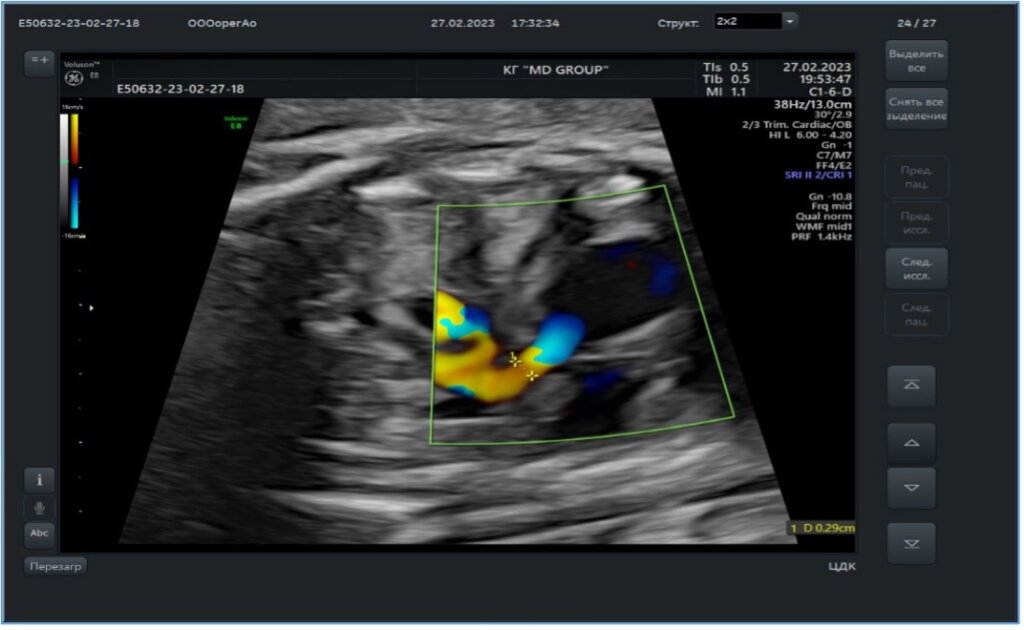

Мандрен извлекается, и заранее подготовленный комплекс проводник/баллон заводится через иглу и проводится в клапан аорты. Для предотвращения кровопотери на иглу устанавливается Y-коннектор (рис.3).

Учитывая малый диаметр иглы, вальвулопластика производится коронарным баллоном. Подбирается баллон по диамету аналогично тому, как это делается при вальвулопластике в постнатальном периоде: диаметр баллона полностью должен соответствовать диаметру фиброзного кольца клапана аорты. После того, как баллон с проводником были заведены в клапан аорты, что нашло подтверждение по данным ЭхоКГ, производится раздувание баллона (рис.4). Важно, что баллон раздувается и перекрывает кровоток через клапан аорты до исчезновения перетяжки и на непродолжительный период времени. После того, как баллон сдут, специалист УЗИ-диагностики проводит оценку вальвулопластики (рис.5) и при положительном результате весь комплекс игла-коронарный проводник-коронарный баллон извлекаются единым блоком. При этом важно помнить, что баллон ни в коем случае не следует затягивать в иглу, т.к. острый срез иглы может привести к повреждению баллона и эмболии мелкими фрагментами.